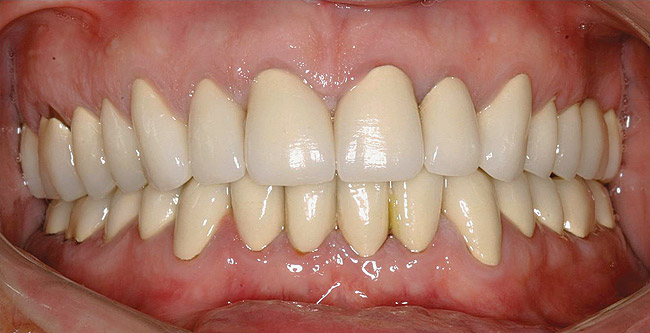

Figure  1  Natural tooth wear.

Figure 1

If the centric relation and centric occlusion in the presence of tooth surface loss is the same, or the dento-alveolar compensation has occurred, the teeth should be restored.54 The restorations can include Class V or palatal restorations, or reproduction of the cusps (Figure 9). Also, restorations can include covering the affected tooth surfaces with resin-based composites, using a sandwich technique, or placement of metallic, porcelain-fused-to-metal, or ceramic crowns (Figure 10, Figure 11, Figure 12, Figure 13, Figure 14, Figure 15 and Figure 16).